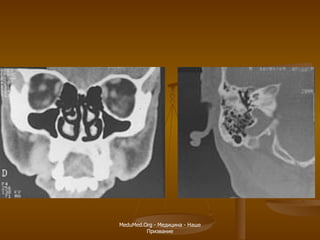

МСКТ - урография Чашечка Лоханка Мочеточник

МСКТ - урографияЧашечка Лоханка Мочеточник